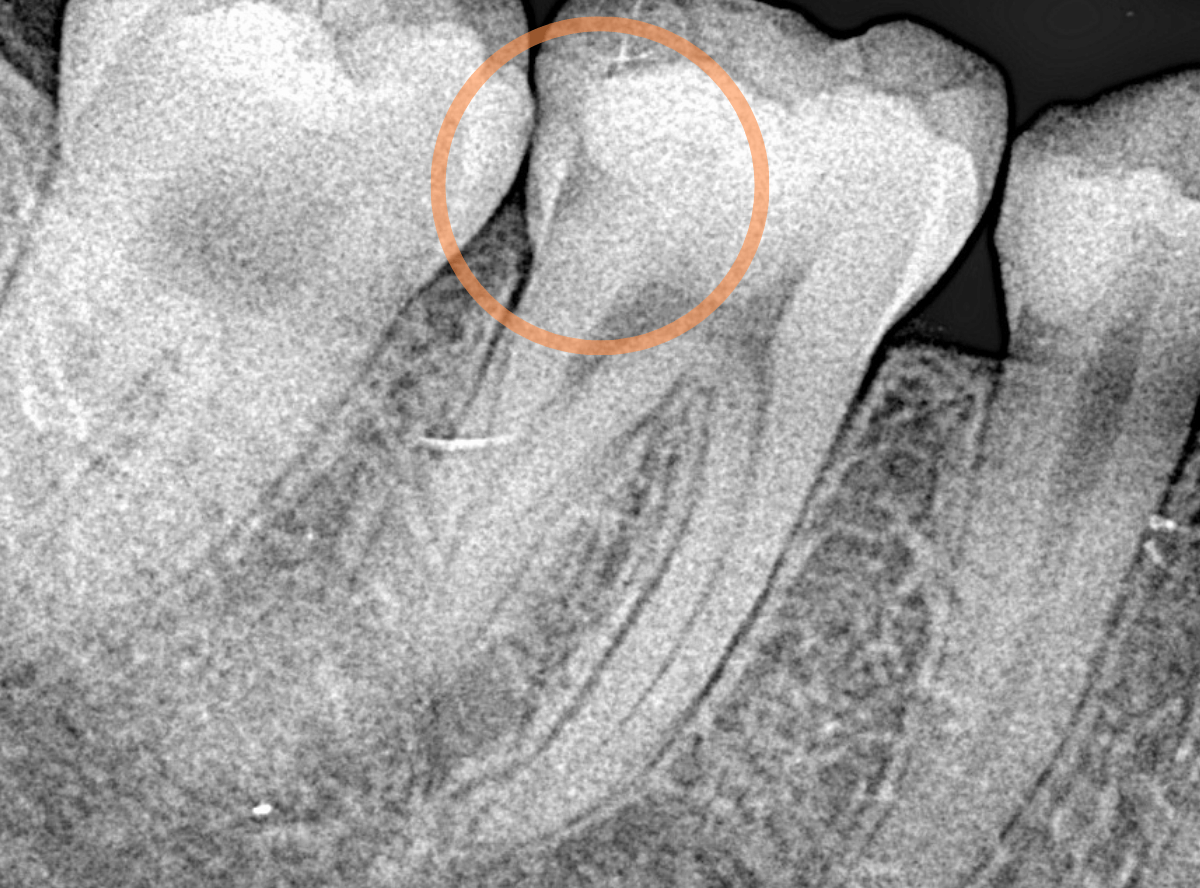

レントゲン写真で確認します。

青い線が神経、赤い線が虫歯の部分です。

前後の歯とも、かなり深く広い虫歯になっているのがわかります。